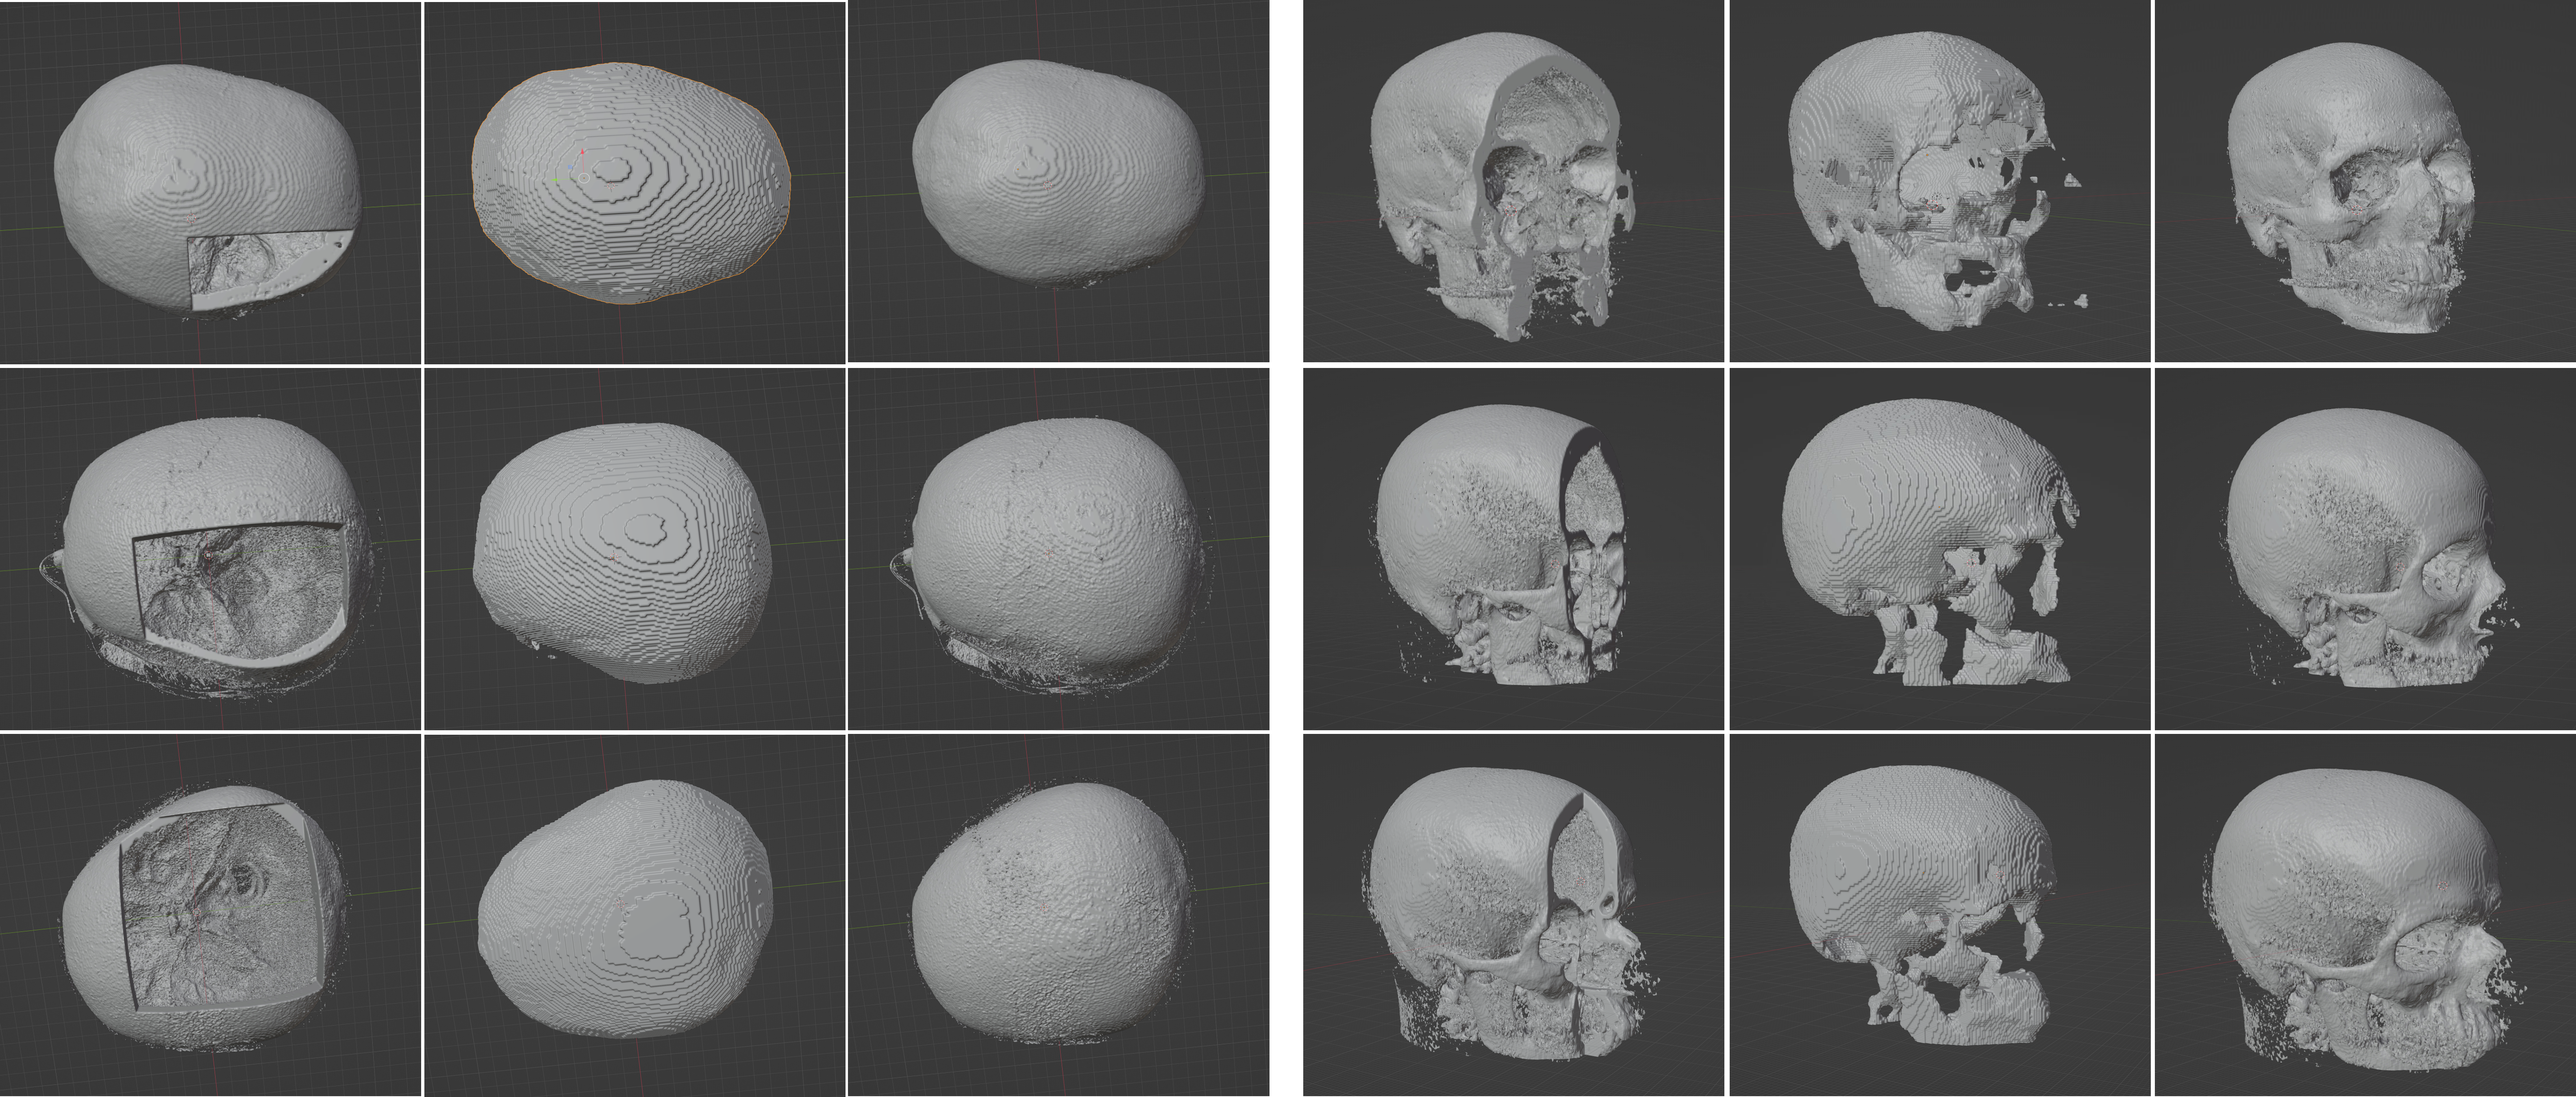

Figure 4 shows the reconstruction of cranial and facial defects for the MUG500+ dataset, using the trained model. We can see that the cranial reconstruction is satisfactory, while the network failed to recover the subtle and complex facial structures. Besides the learning capacity of the network, we attribute the unsatisfactory facial reconstruction performance largely to the MUG500+ dataset itself, as the MUG500+ skulls have obvious artifacts (e.g., spine, catheter extruded from the patients’ mouth, etc, as can be seen from the last column of Figure 4.) that can potentially distract the network from learning the skull geometries. The removal of these artifacts in a preprocessing procedure is non-trivial, since they are closely connected with the skull, and therefore difficult to be separated from the area of interest (e.g., facial bones). One option to better utilize the dataset for cranial implant design is to crop (axially) and discard the entire facial area of the skulls as in [15].

On the contrary, the SkullFix dataset contains mostly artifacts-free skulls, and is more suitable for the facial reconstruction task than MUG500+. The last column in Figure 5 shows skulls with facial defects. We can see that part or the entire facial structures are missing. The first to third column in Figure 5 show the facial reconstruction results obtained using the trained network. Note that the initial reconstruction and the input are misaligned (first column, Figure 5), and therefore the missing facial bones cannot be obtained via a subtraction procedure. We address this by registering the reconstructed completed skull with the input defective skull using a similarity transformation. The second column in Figure 5 shows the geometry alignment results. Note that the registration is unsuccessful for some cases. The third column in Figure 5 shows the facial reconstruction in 3D. We can see that, compared with the results on MUG500+, the network can learn to restore most of the missing facial structures on the artifacts-free dataset more effectively. Note that the registration step could be avoided by properly aligning the geometry information in the NIfTI output from the model with that of the original NRRD test samples.A 3D viewer for interactive inspection of the skull models can be accessed at https://proj-page.github.io/softwarex_monai.html.